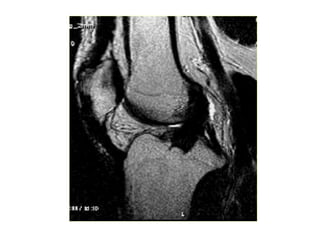

LCL

MCL, ITB